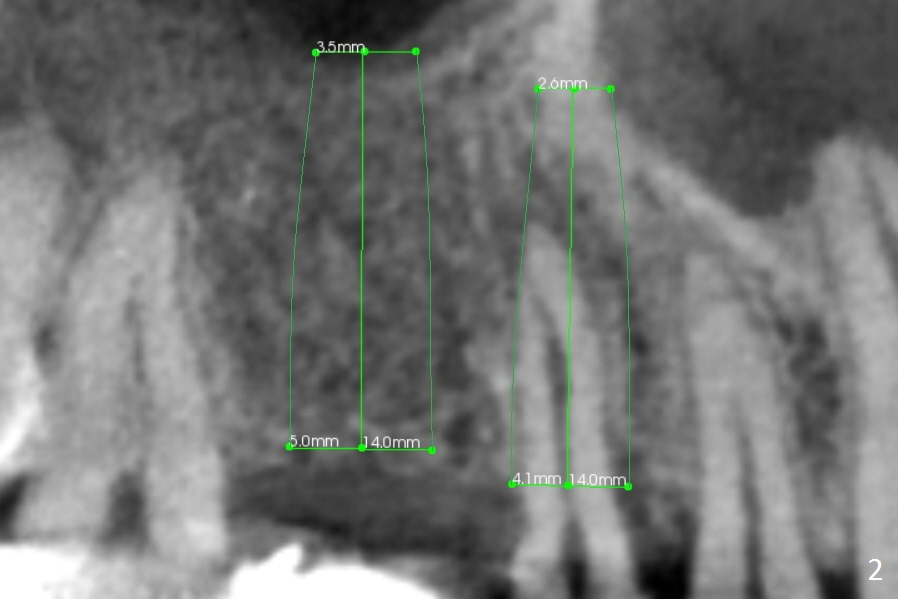

After implant at #19 and RCT at #14, the 36-year-old woman has discomfort in the upper right quadrant due to caries at #4 (Fig.1 *). After sectioning the bridge between #2 and 3, the retainer at #4 should be separated from the abutment by itself because of severe caries. Also examine the salvageability of #2. If the tooth #4 is nonsalvageable (Clindamycin), two implants will be placed at #3 and 4 (Fig.2-4). Since the ridge at #3 is wide (Fig.3, coronal section (B; buccal)), use Magic Split to start osteotomy, followed by Magic Expanders. The initial depth at #3 will be 12 mm and gradually increase to 14 mm. On the other hand, the bone density is higher at #4, drills will be used for osteotomy. Speed will be reduced at 50 RPM when the drills are more than 3.8 mm. Take intraop PAs as early as possible for trajectory confirmation.